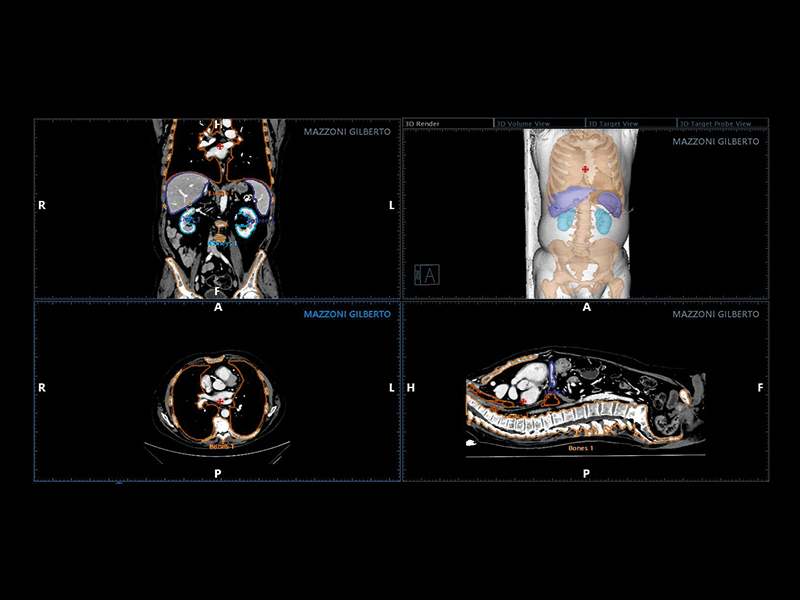

Virtual Navigator (VNav), as the most advanced Esaote Fusion Imaging technology supported by Artificial Intelligence, is opening new horizons in cross-modality liver imaging. Virtual Navigator provides a very simple and active coupling of ultrasound examination with a second Dicom modality imaging (MRI/CT/Pet-CT) dataset as a reference. It enables real-time navigation to benefit from both modalities to increase confidence and accuracy throughout interventional procedures on the liver.

Virtual Navigator, supported by A.I., simplifies abdominal fusion thanks to the exclusive AutoSync function that enables automatic registration based on 3D camera technology. As a historical expert in fusion imaging, Esaote offers you a comprehensive package of tools to significantly reduce the complexity of interventional procedures and increase confidence in the information obtained with your ultrasound device.

• Augmented reality visualisation of the abdominal organs

• Automatic movement correction

• Needle tracking

• Advanced planning software

• CEUS, elastosonography, microV compatibility

• Automatic registration via omniTRAX™